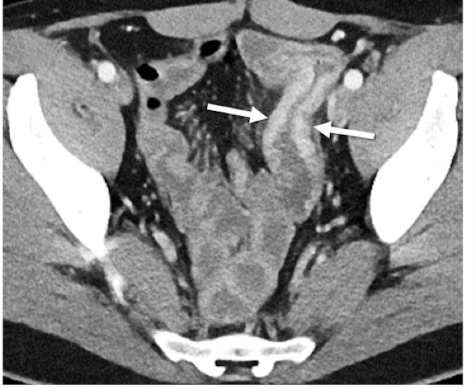

What is this and what type of scan

crohns, CT